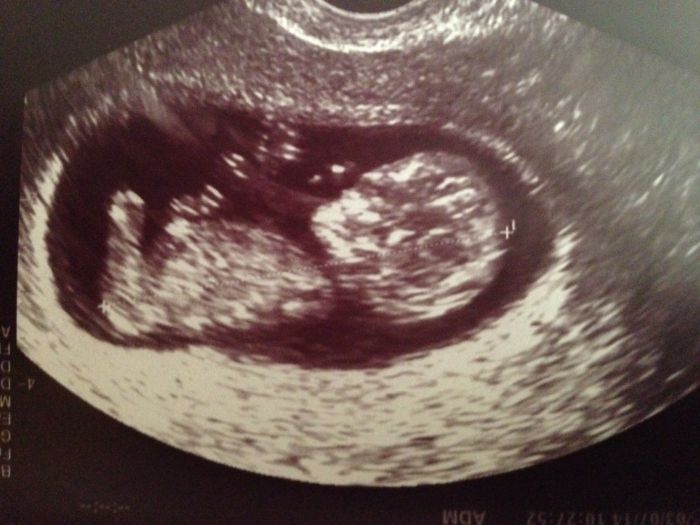

Ahoj holky tak se zase hlasim po delší době dnes sem byla na kontrole a na krvi u dr a v pondeli jdu na screening taky jsem se objednala k jinemu doktorovi muj gynekolog ho sice dela ale chce za nej 1500kc a nema ani certifikat takze vim prd zda je to pak stoprocentni takze jdu nakonec za 1000kc k jinemu kde budu mit i utz natoceny na usb a hlavne jistotu kvality ;) jinak po dnesni kontrole vse v poradku termin sedi jak podle utz tak podle PM na 22.1. cili 11+0 dnes ;) a vse v poradku mame se cile k svetu a merime 4,35cm ;) prikladam dnesni foto ;) a drzim palecky vsem co jdou na kontrolu ;)

[582427] Terezko, to je krásná fotka! Všechno jde krásně poznat

už se taky moc těším na svoji, už to není fazolka ale regulérní človíček

Dekuju, jj jsou to uz uplny miminka je krasny na ne koukat jak uz si tam kopou a machaj rucickama ;)